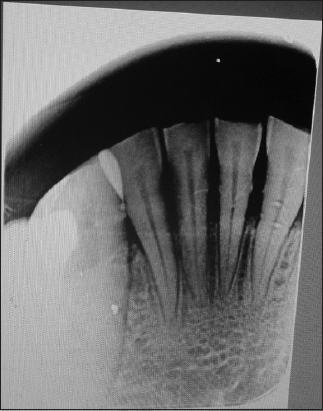

On palpation, the growth was smooth and nontender, with no evidence of pus or superficial ulceration. Periapical radiographs of #32 and #33 revealed a widening of the periodontal ligament space [Figure 3]. The clinical differential diagnoses of POF are pyogenic granuloma, and irritation fibroma. Fibroma was indicated as a preliminary diagnosis. Periodontal health is a requirement for successful treatment outcomes.[8] The patient had moderate calculus and mild gingival inflammation. Oral prophylaxis and oral hygiene instructions were provided as part of Phase 1 therapy. The patient was recalled after 2 weeks to review periodontal maintenance and resolution of gingivitis. There was no change in the size of the lesion.

Figure 3: Intra oral periapical radiograph